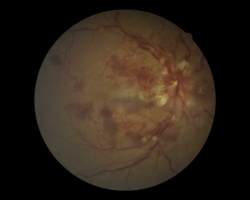

- OD : œdème papillaire, hémorragies en flammèche, en tâches, profondes et superficielles, nodules cotonneux, veines dilatées tortueuses. Existence d’un œdème maculaire aussi.

- OG : normal